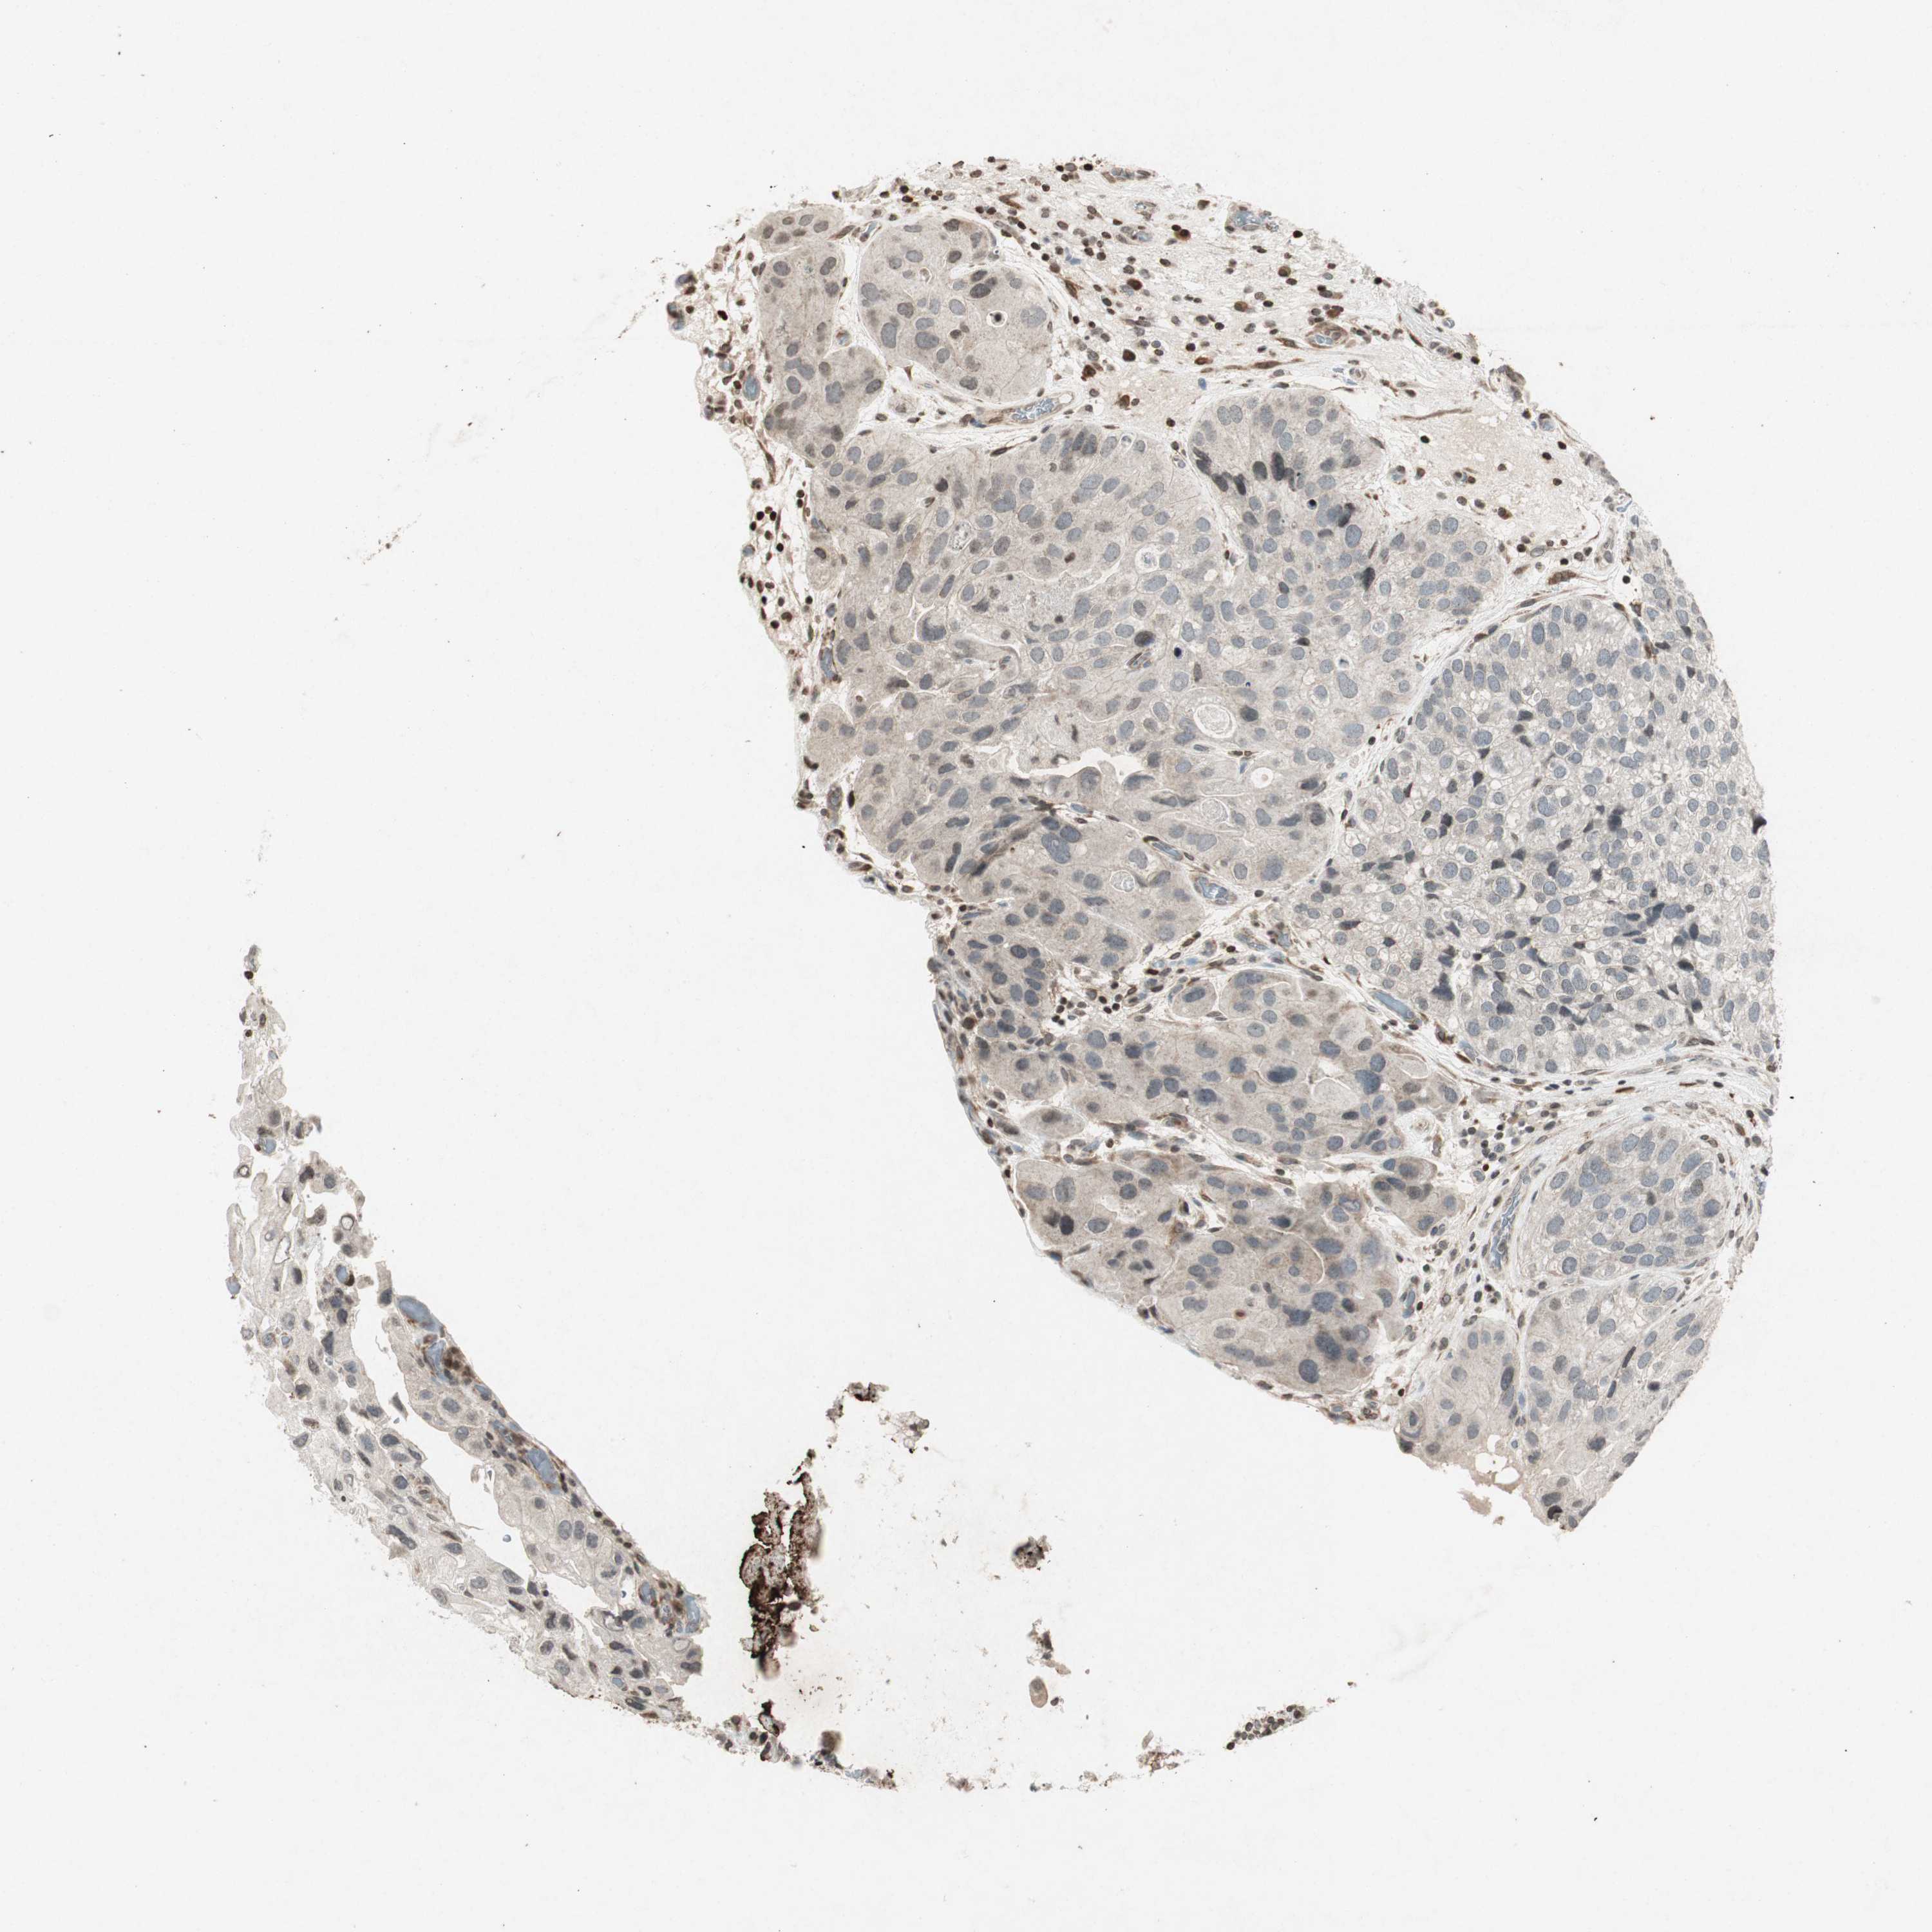

UROTHELIAL CANCER - Protein expressioni

A mouse-over function shows sample information and annotation data. Click on an image to view it in a full screen mode. Samples can be filtered based on level of antibody staining by selecting one or several of the following categories: high, medium, low and not detected. The assay and annotation is described here.

Note that samples used for immunohistochemistry by the Human Protein Atlas do not correspond to samples in the TCGA dataset.

Antibody stainingi

Antibody staining in the annotated cell types in the current human tissue is reported as not detected, low, medium, or high, based on conventional immunohistochemistry profiling in selected tissues. This score is based on the combination of the staining intensity and fraction of stained cells.

Each image is clickable and will lead to virtual microscopy that enables deeper exploration of all samples and also displays staining intensity scores, fraction scores and subcellular localization as well as patient and tissue information for each sample.

Antibody HPA007699

Antibody CAB009629

Urothelial carcinoma, High grade